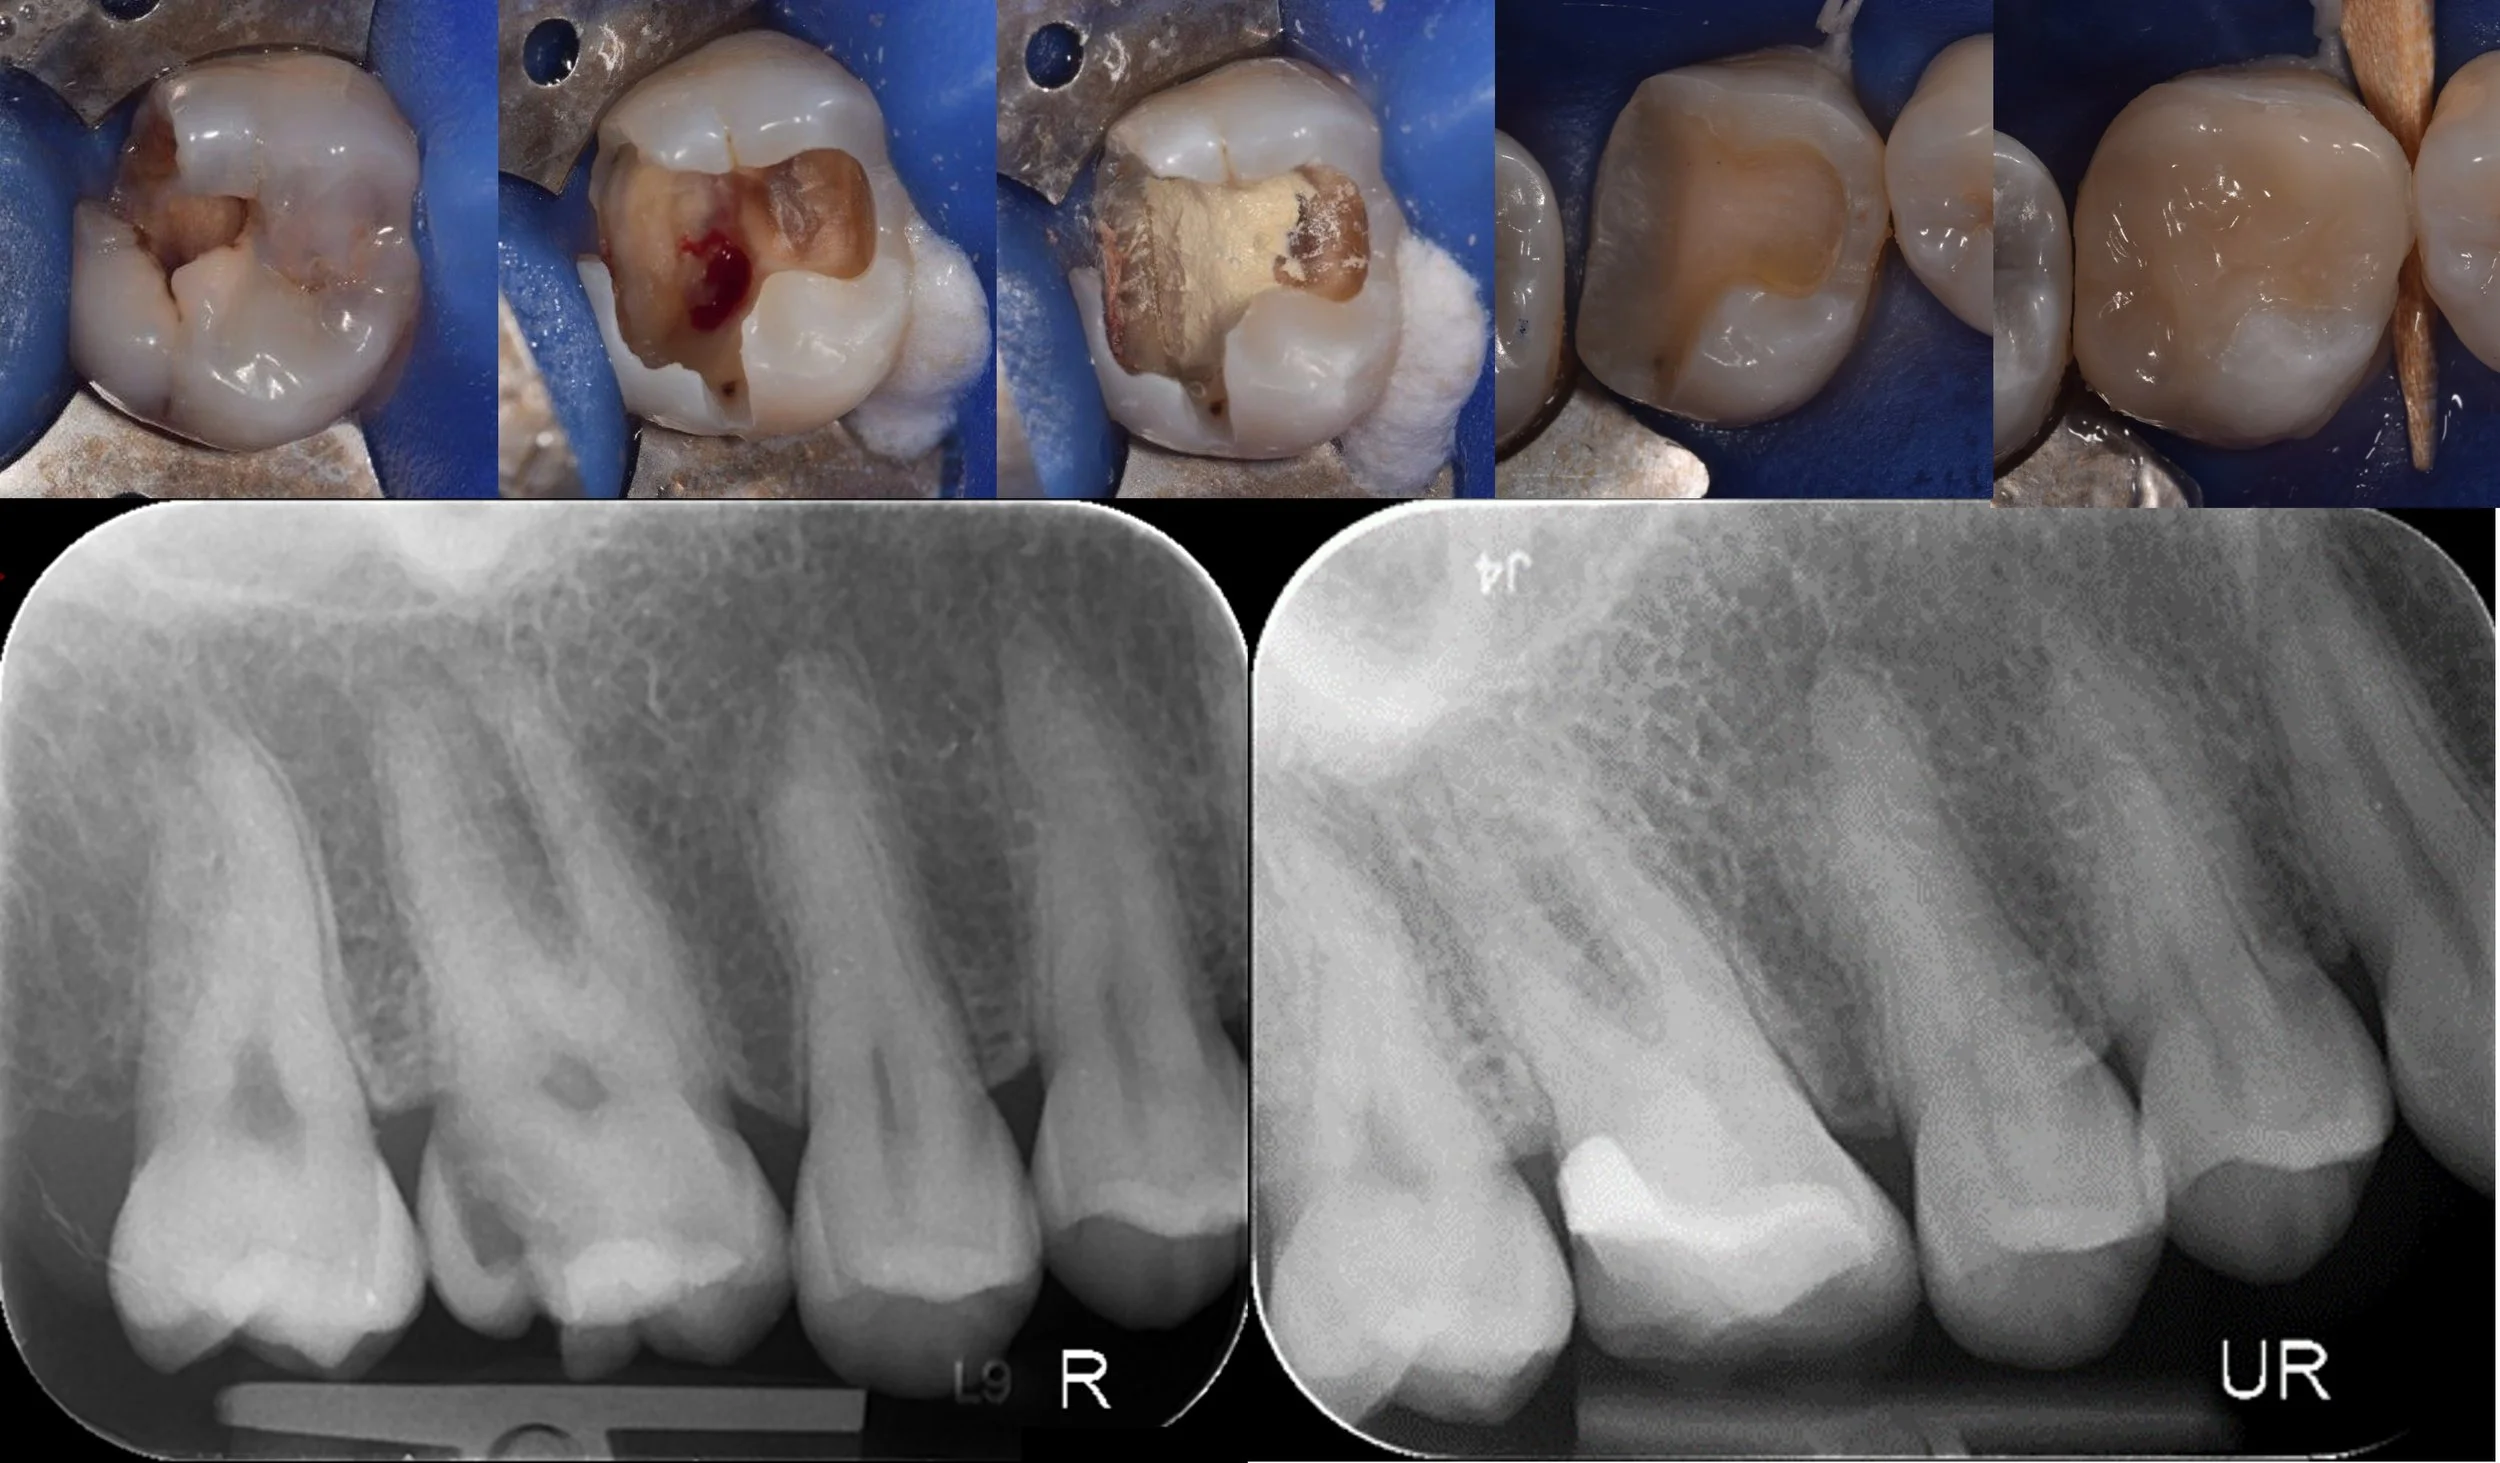

Precision root canal treatment under microscope.

All procedures completed under operating microscope — using the latest evidence-based techniques and premium materials for outcomes that last.